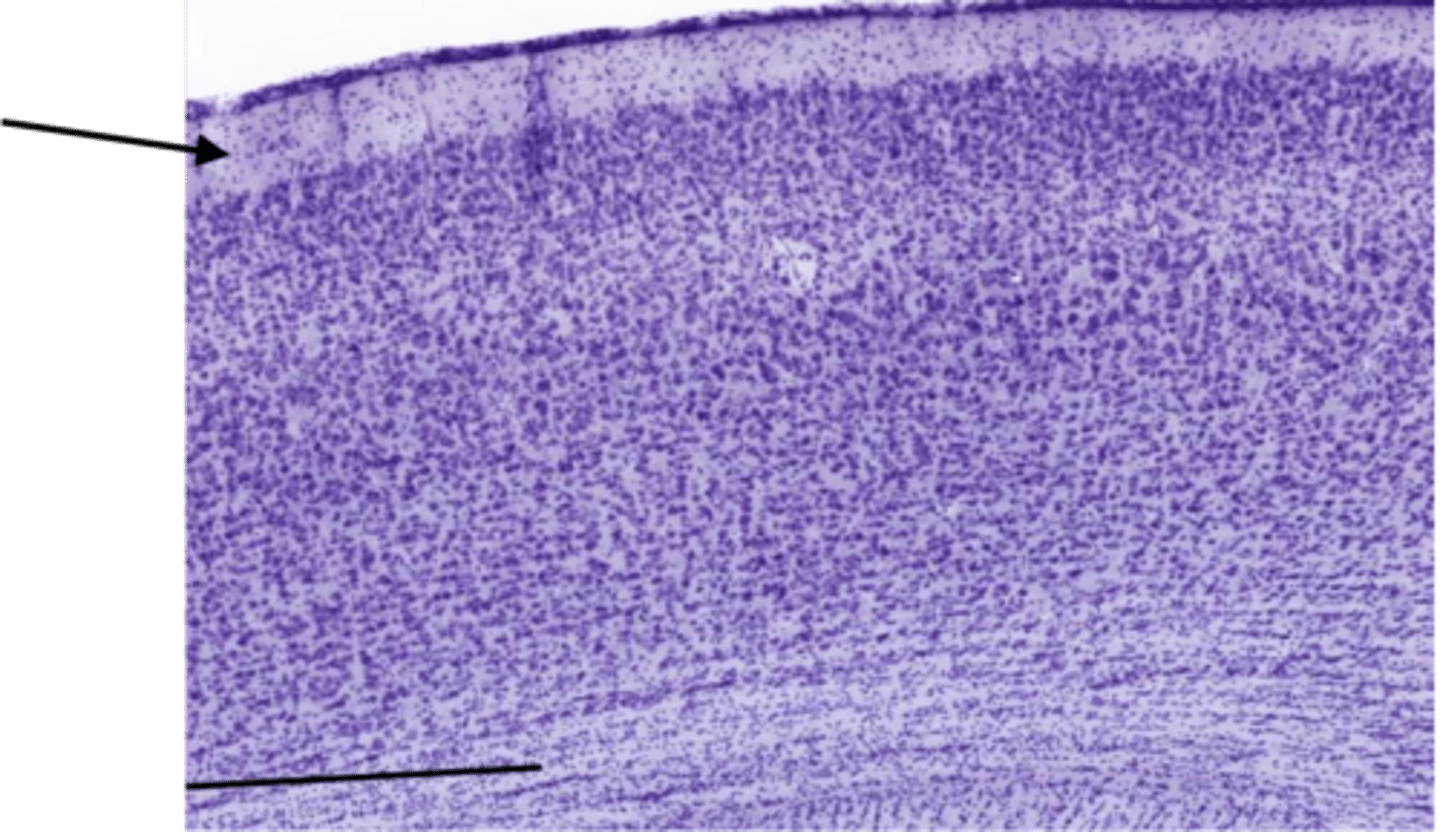

Identify the layer of the cerebrum

molecular layer

pia mater

arachnoid

pyramidal layer

white matter